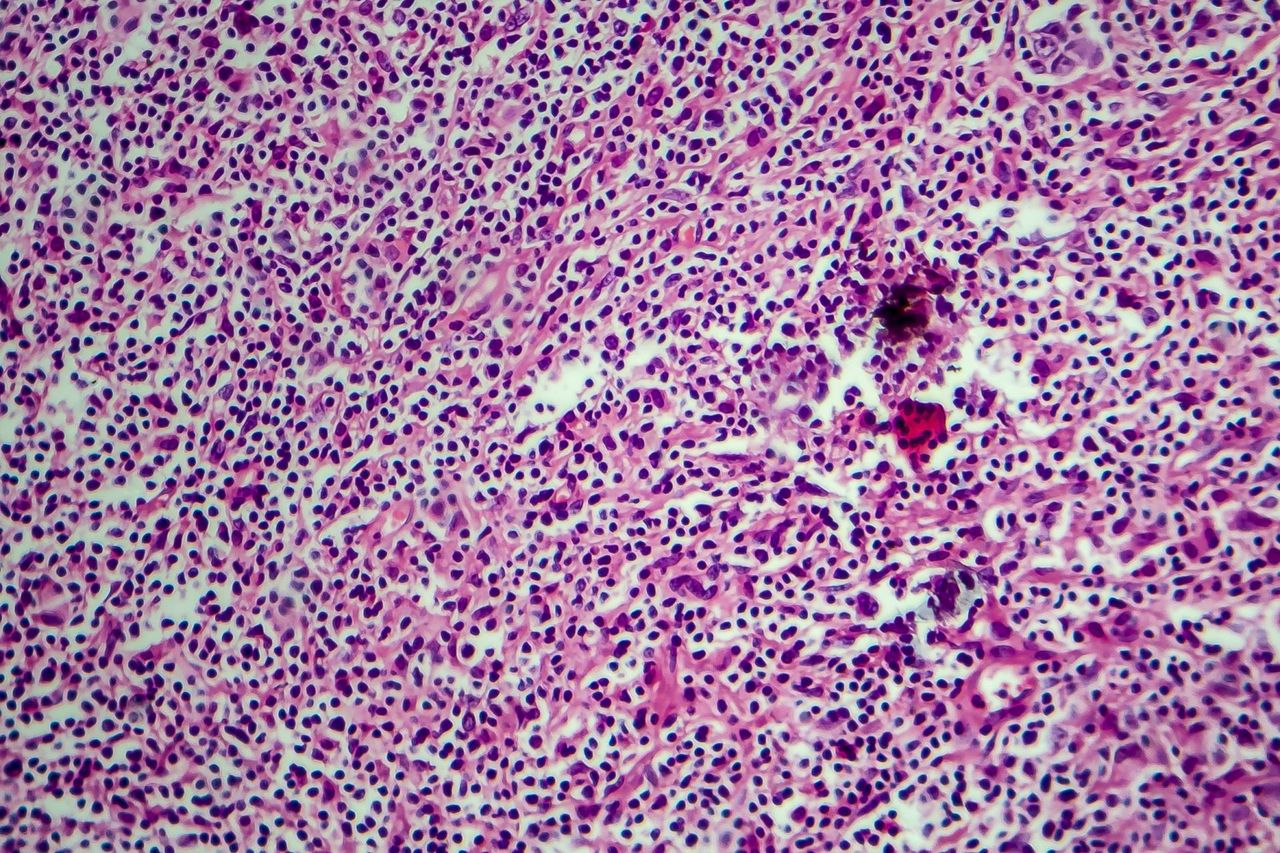

Chłoniak Hodgkina to choroba nowotworowa węzłów chłonnych. Objawy w początkowym etapie przypominają ostre lub przewlekłe zakażenie jamy ustnej bądź gardła. U 90 proc. pacjentów można zauważyć powiększenie węzłów chłonnych szyi.

Powiększenie węzłów chłonnych może być jednym z objawów chłoniaka